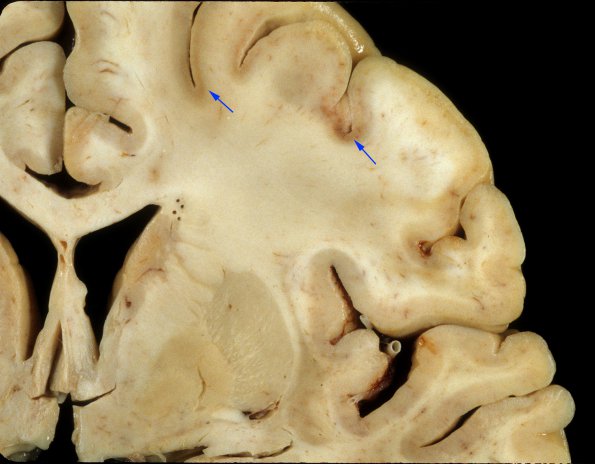

Higher magnification shows focal discoloration and thinning of the cortical ribbon which is exaggerated at the depths of some sulci, often considered to represent a hypoxic/ischemic pattern of injury.